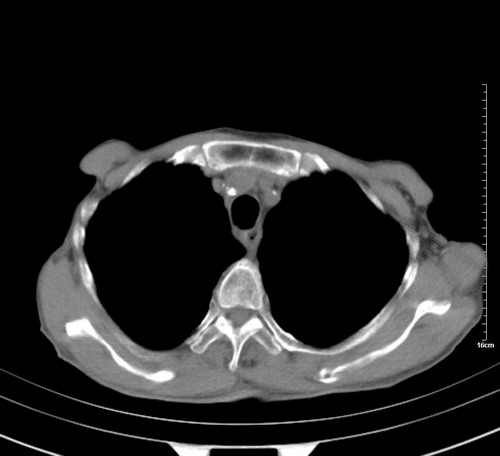

病人,女,79岁,主要因腹疼二月入院,彩超,肝,胆,脾,未见异常,胸透上消化道造影未见异常,化验白细胞增高,内科医生让做胸部ct检查,因为熟人多做了腹部(外科会诊考虑胆囊炎).现ct片如下请假各位战友.

中后纵隔占位,气管、食道受压、变形、移位。恶性可能性大。

考虑:中后纵隔转移瘤可能性大,主动脉硬化。

中后纵隔占位, 考虑:转移瘤不除外.

纵隔淋巴结肿大,考虑转移而来

肺癌,纵隔淋巴结转移,肝左叶病变考虑为转移病灶。

建议强化检查,考虑纵隔型肺癌,小细胞可能性大。